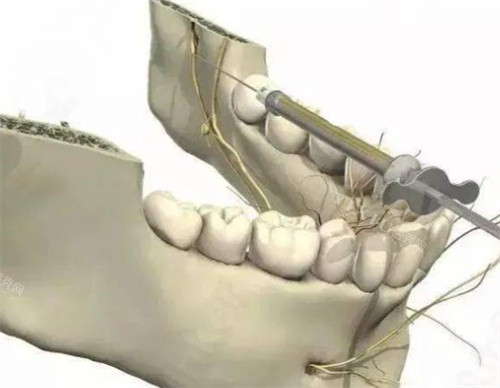

初到牙仙子口腔,前台的工作人员热情地接待了我,引导我进行登记并安排了正规的口腔医生为我检查。给我看诊的医生有着丰富的临床经验,在仔细查看了我的牙齿情况,并借助新型的智能化口腔 CT 机进行详细分析后,耐心地为我讲解了全瓷牙修复的方案。他不仅正规知识扎实,还非常有耐心,对我提出的各种问题都一一解答,让我原本紧张的心情逐渐放松下来。

经过一段时间的等待,我的全瓷牙终于安装好了。不得不说,结果真的超出了我的预期。全瓷牙的色泽与我原本的牙齿非常接近,自然美观,几乎看不出来是修复过的。而且在佩戴后的使用过程中,感觉和自己的真牙无异,咀嚼功能完全改善正常,也没有出现任何不适的情况。